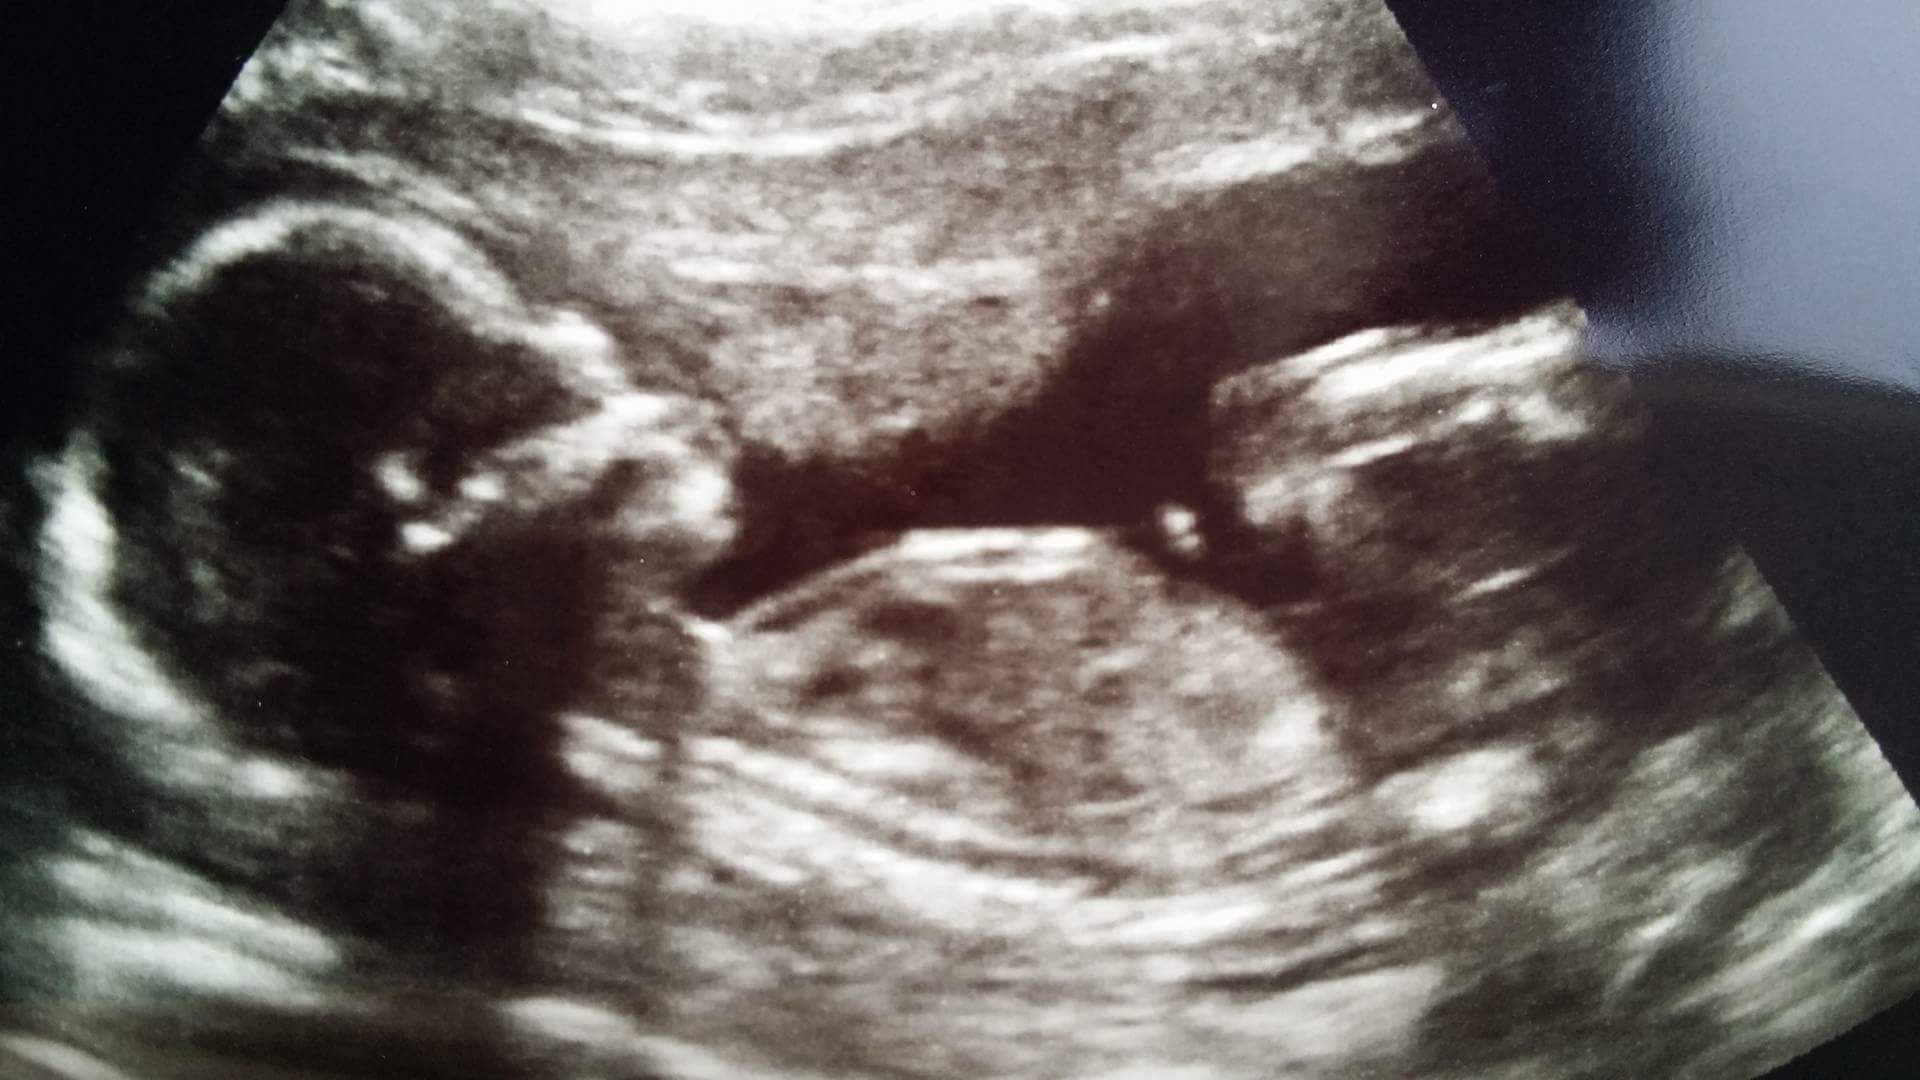

:biggrin2: a to moja kruszyna z dziś :biggrin2:

• received_10208282011201777.jpeg

138,7 KB · Wyświetleń: 457

Katerineczka-slodziutkie to Twoje bobo:-) moze to dziewczynka hihihi:-)